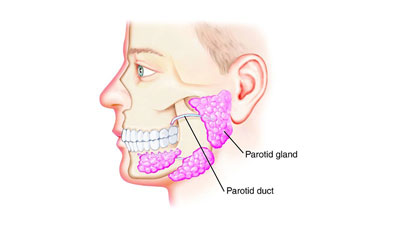

جراحی غده پاروتید یا غدد بزاقی

جراحی غده پاروتید یا غدد بزاقی یک فرآیند جراحی است که برای برطرف کردن مشکلاتی در غده پاروتید (غدههای بزاقی بزرگتر) یا غدههای بزاقی (مانند غدد سلیولر و زیرزبانی) انجام میشود. این غدهها مسئول تولید و ترشح بزاق برای یلتخوردن غذا هستند.